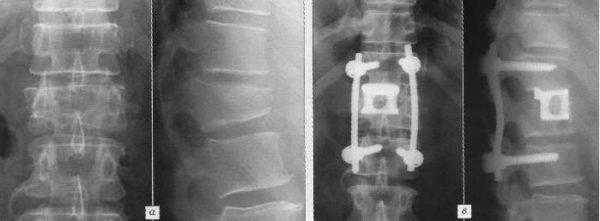

Кейджы межпозвоночных дисков поясничного отдела.

Стабилизация поясничного отдела.